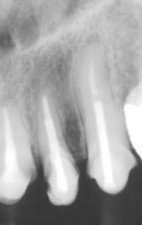

Sobre los términos raíz y corona clínica, quiero

aclarar que la primera se extiende desde apical hasta la cresta ósea y la corona

clínica, desde la cresta ósea hasta oclusal o incisal (Fig. 9) (27), es decir,

que corona clínica no es sólo “lo que vemos clínicamente”, y por tanto

sólo la podemos ver y medir en una radiografía.